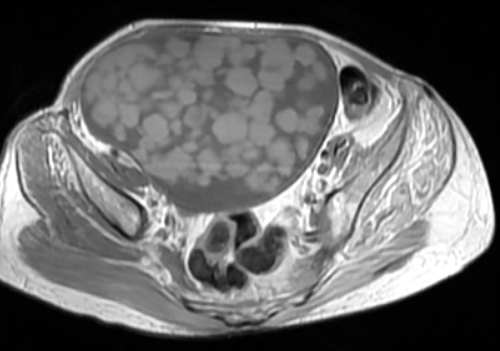

Balls of fat-Dermoid Cyst

This is a case of mature ovarian teratoma with multiple fat balls seen as high signal on T1 weighted MRI images. The fat globules in literature have been described as being 1.5–2 cm in diameter and composed of cheese-like sebum and hairs. In the reported cases, fat globules have occurred in rather large cysts so the fat balls might require sufficient space for their formation. Whether globule formation occurs in both benign and malignant cysts is not known.